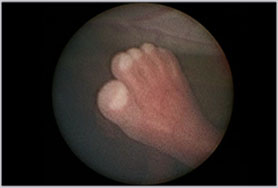

Las caries son una enfermedad infecciosa, que se caracteriza por la pérdida progresiva de los minerales que forman los tejidos del diente (desmineralización). Así éstos quedan expuestos a la acción permanente de las bacterias de la boca, las que producen ácidos a partir de la fermentación de los hidratos de carbono presentes en los alimentos.

La odontóloga María Consuelo Fresno, de Clínica Alemana, explica que este proceso puede detenerse y ser reversible, pero cuando se producen ataques repetidos de ácidos es posible que surjan las caries, las que pueden ir desde una mancha o cambio de color hasta una cavidad en la pieza afectada.